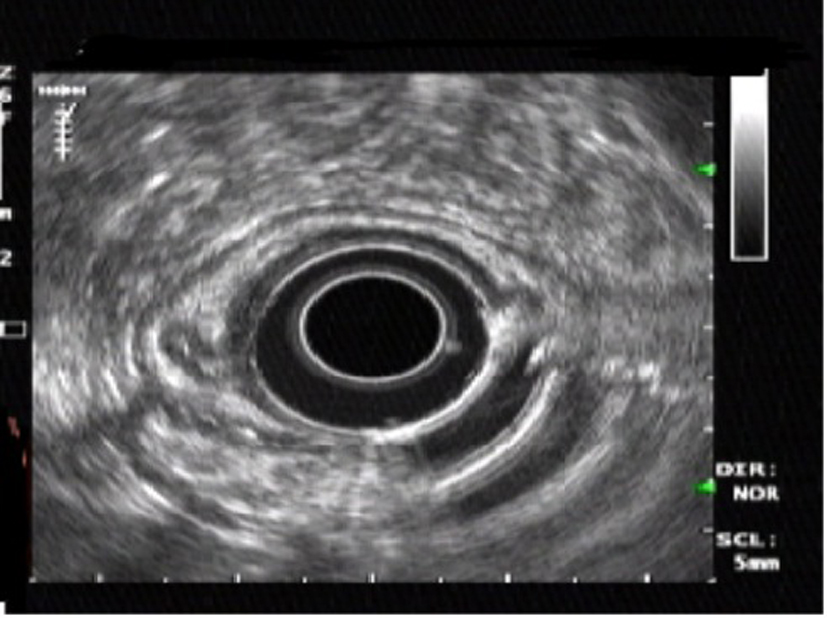

A 54-year-old Nigerian woman was referred to our department for further evaluation of abdominal pain. She had no remarkable past medical history and no history of alcohol consumption, smoking and drugs. She underwent endoscopic examination during a routine checkup. Upper GI endoscopy was performed and revealed a small submucosal lesion of about 1.2 × 1 cm in diameter, located on the lesser curvature of the gastric antrum. The esophagus, duodenum and the remaining parts of the stomach were normal. Upon hospitalization, physical examination, biochemical parameters were completely normal. Endosonography demonstrated a homogeneous, hypoechoic, clearly demarcated 1.2 × 1 cm mass, which was confined to the submucosal layer and above the muscularis propria (Fig. 1). It was challenging to confirm the diagnosis. Because the tumor was relatively small in size, it was considered for endoscopic resection.

![]() Click for large image | Figure 1. Endoscopic ultrasonography showing a homogeneous, hypoechoic, clearly demarcated mass in the submuscosal layer. |